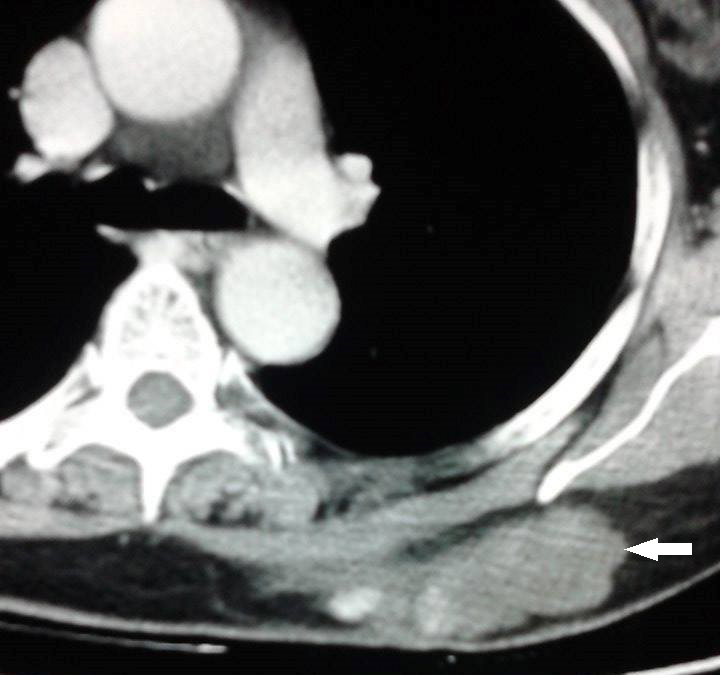

Mr BS, aged 52, had as a complaint of left para-sternal chest pain of moderate intensity without radiation. The clinical examination revealed a patient in good general condition without associated comorbidity. Chest CT scan showed an anterior mediastinal mass (Figure 4) with both tissue and fatty components of 81x75x16 mm not enhanced after contrast injection invading the pericardium and heart muscle with pericardial and bilateral pleural effusion more marked on left. CT brain, abdominal and pelvis showed no distant metastasis. Echocardiography showed a normal heart compressed anteriorly by a tissue mass. Assays of AFP and β-HCG were normal. Exploration by left parasternal mediastinoscopy was decided at first. After a 3 cm incision, exploration by mediastinoscopy showed an anterior mediastinal hard mass fixed to the pericardium. Several biopsies were performed. The pathological and immune his to chemical results were in favor of pleomorphic liposarcoma grade II according to the classification of the FNCLCC. After discussion of the Thoracic Oncology Group on medical file, indication for radiotherapy was made.

Figure 4 Anterior mediastinal mass (white arrow) with both tissue and fatty components of 81 x 75 x 16 mm not enhanced after contrast injection invading the pericardium and heart muscle.